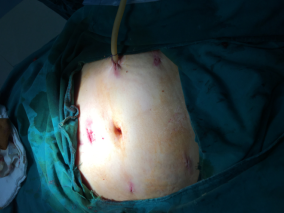

?我院成功開展腹腔鏡下“子宮廣泛切除+盆腔淋巴結(jié)清除術”?近日,我院成功為一位宮頸癌早期患者實施了腹腔鏡下“子宮廣泛切除+盆腔淋巴結(jié)清除術”。本次手術的成功開展,標志著我院婦產(chǎn)科腹腔鏡手術技術達到了市級同行的領先水平。?危險:陰道不規(guī)則出血 ?竟是癌魔來襲39歲的患者王女士(化名),2年前曾因“宮頸...